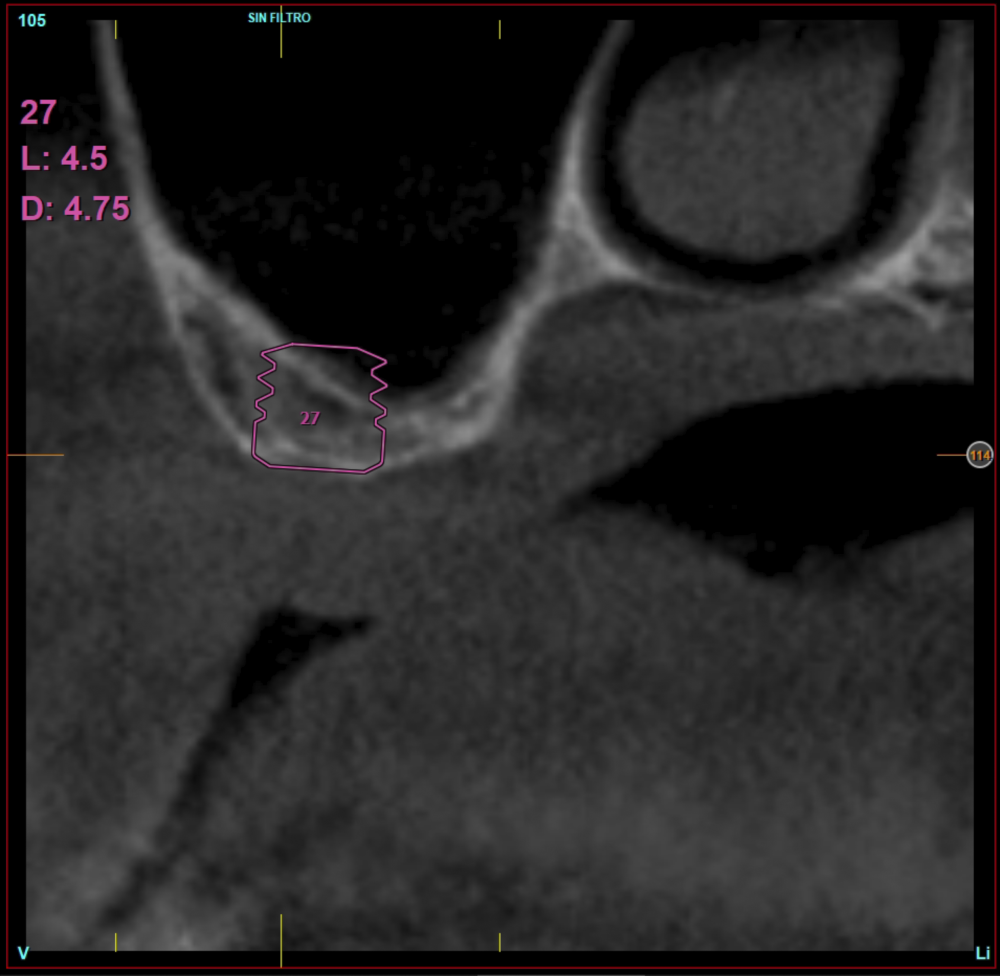

In all cases, a diagnosis was made based on study models, intraoral examination of the patient and performing a Cone-beam analysed using the specific BTI-Scan 3 software (Biotechnology Institute, Vitoria, Alava, Spain).

Patients attend subsequent check-ups performing a control Cone-Beam after 5 months (before loading the implant) and after one year of the load, performing a new measurement in these images to analyse the bone gain and the maintenance of the same. In these check-ups, data are collected on prosthetic complications or crestal bone loss in these patients, as well as possible failures.

Ten patients who met the inclusion criteria were recruited, in which 20 implants were inserted. Three of them were women with an average age of 72 (+/- 6 years). None of the patients were smokers at the time of surgery and did not have any active periodontal disease. The majority of the implants diameter included in the study was 5 mm (60%), followed by 4.5, 5.5 and 4.75 mm (13.33% each). The predominant length was 5.5 mm (86.6% of the cases), with 13.4% of the remaining implants with a length of 4.5 mm. The most common positions were for the second molars (molars 27 and 17) representing 55% of the cases.

The mean height of the residual bone volume was 3.1 mm (+/- 0.3 mm with a range of 3-4 mm). In all cases, transcrestal sinus elevation was performed, with particulate autologous bone obtained from milling the neo alveolus generation zone for implant insertion, being the average of this elevation above the apex of the implant of 2.8 mm (+/- 0.99 range 1.9 -5 mm). In the CT control scan after one year of inserting the studied implants, the bone gain achieved was maintained, no decrease in the volume gained was observed, only three cases showed a decrease of between 0.4 and 0.5 mm of the initial volume at the end (Table).

Figures 2-19 show one of the cases included in the study.